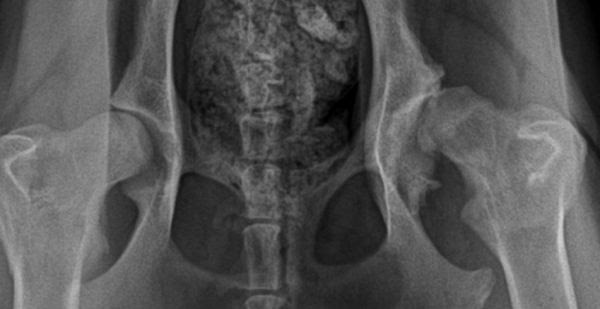

Bailey Frost diagnosed with HD March 18, 2011

original X-Rays

FHO Surgery was recommended and selected

Post Surgery X-Rays